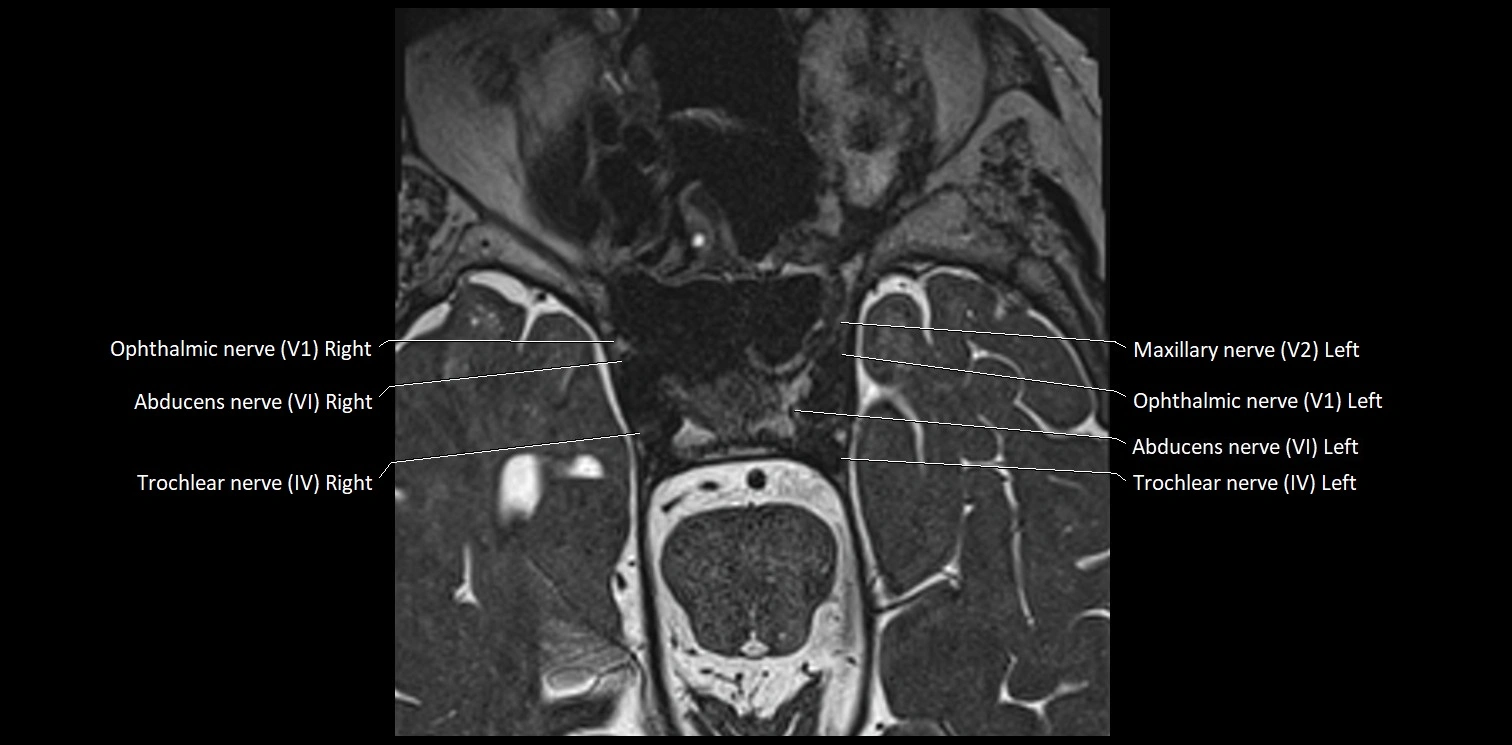

MRI images

image